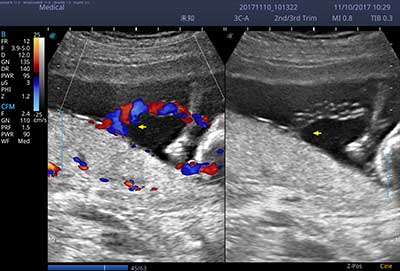

E3便携式彩色多普勒超声诊断系统拥有专业超声技术平台、高度集成化的硬件模块和结构设计、简便的操作流程、支持三探头接口全激活,兼顾了优质图像、轻便机身以及台便两用的临床使用需求。无论在常规超声科门诊检查,还是在急诊、麻醉、ICU、户外等各种应用场景。都能给您带来流程的操作体验。